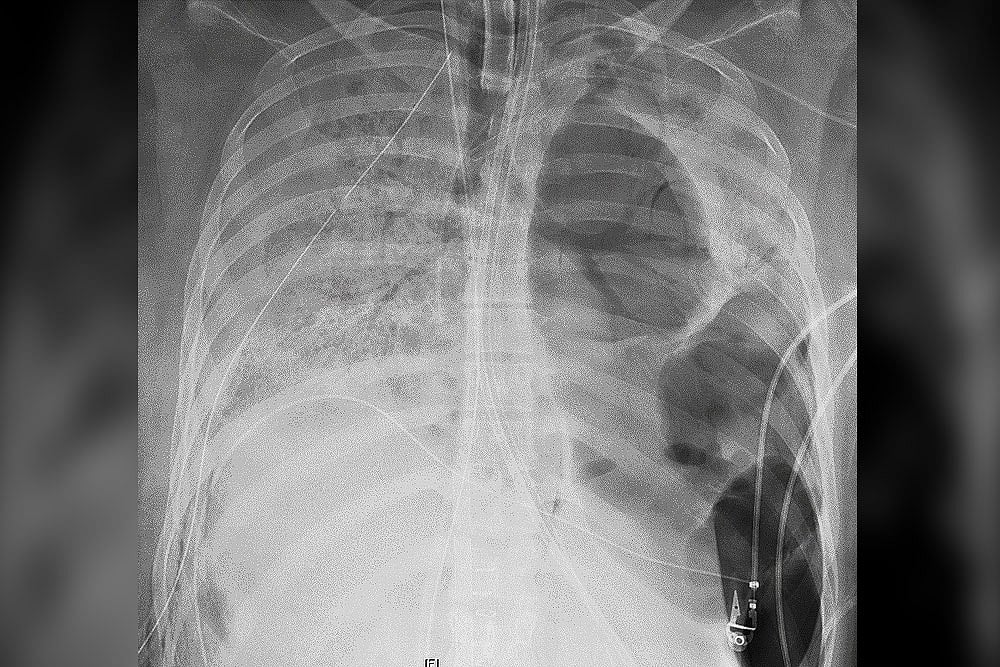

The patient spent six weeks in the COVID ICU on a ventilator and extracorporeal membrane oxygenation (ECMO), a life support machine that does the work of the heart and lungs, the hospital said.

By early June, the patient’s lungs showed irreversible damage. The lung transplant team listed her for a double-lung transplant, and 48 hours later, performed the life-saving procedure at the hospital.